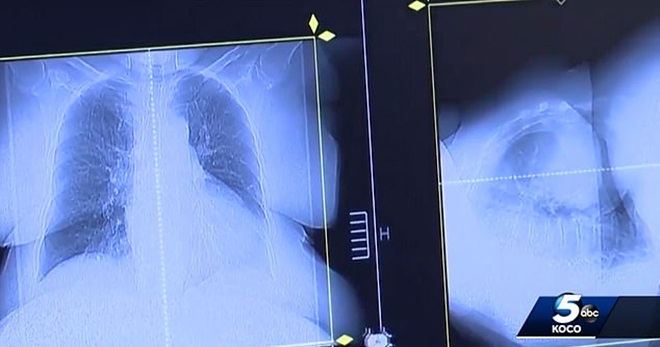

根据《Daily Mail》报导,提濆斯受访说,2017年1月收到噩耗时,「正子断层扫描」显示,癌症已经扩散到他的肝脏,胰腺,膀胱,胃,颈部和骨骼,但德州MD安德森癌症中心(MD Anderson Cancer Center in Texas)的医师们告诉他,他们不会放弃,并且要让他参加1个「可能可以存活1年」的临床实验。

再过了2周半后,提濆斯又进行了1次「正子断层扫描」,结果发现,所有的癌症都消失了!这个状况让MD安德森癌症中心的医师们目瞪口呆!因为,参加临床实验的癌症病患中,只有提濆斯有这种反应。